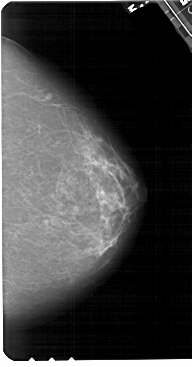

A_1552_1.LEFT_MLO

A_1552_1.LEFT_CC

LEFT_CC LINES 5401 PIXELS_PER_LINE 2956 BITS_PER_PIXEL 12 RESOLUTION 43.5 OVERLAY

LEFT_MLO LINES 5491 PIXELS_PER_LINE 3436 BITS_PER_PIXEL 12 RESOLUTION 43.5 OVERLAY